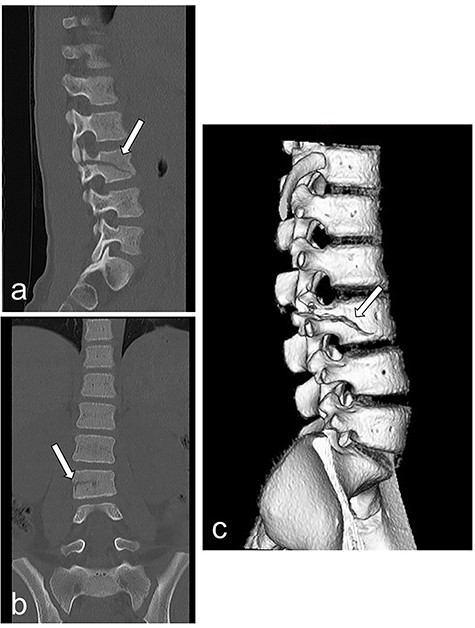

Radiography and CT on hospital day 1. (a, b) Radiography shows fracture of the lumbar spine at L3. (c) CT shows a fracture of the lumbar spine at L3.

A 10-year-old girl was sitting in the back seat of a right-hand drive car, behind the driver, when another car came from the front and bumped into the patient’s car on the right side. The patient was restrained in a three-point seat belt (shoulder and lap belts). She was transferred to our hospital, where she was alert and communicative on arrival. Her chief complaint was abdominal pain. She was 137-cm tall and weighed 30 kg. On presentation, her heart rate was 87 beats/min, her blood pressure was 123/62 mm Hg, her respiratory rate was 20 breaths per minute, her oxygen saturation was 100% and her temperature was 36.7°C. A seat belt sign was observed, with contusions on the forehead and the right iliac region. Her abdomen was tender and she displayed guarding. Focused assessment with ultrasonography for trauma showed a fluid collection in the pelvic cavity. Enhanced computed tomography (CT) demonstrated no free air but confirmed the presence of a fluid collection in the pelvic cavity (Fig. 1a and b). Radiography and CT showed a fracture of the lumbar spine at L3 (Fig. 2a–c).